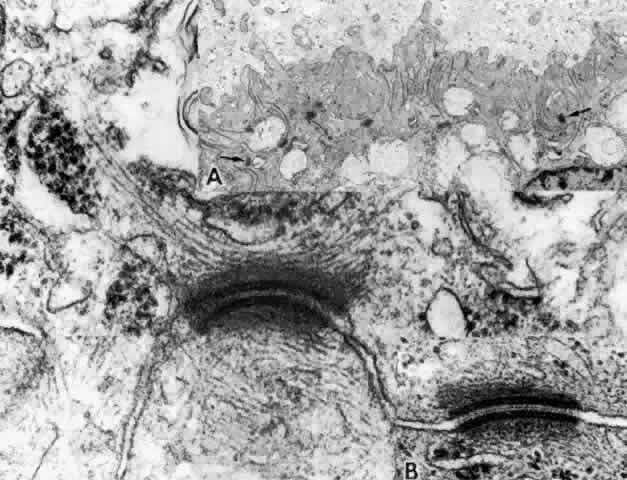

The zonula occludens is the primary component of the blood-aqueous barrier “tight junction.” It appears as a focal area at which the bilayered plasmalemmal membranes of each cell surface are tightly joined (Fig. 20). Zonular adherens junctions occur adjacent to occludens junctions on the basal side. They show a 12- to 15-nm space between the adjoining cells, with filamentous matrix material clinging to the cell membranes on either side. By the freeze-fracture technique, the zonula occludens consists of branching anastomosing strands on the cytoplasmic side of the plasmalemmal membrane (P-face) and matching grooves on the external side (E-face), giving a quilted effect (Fig. 21). The variation in number of strands seen from area to area in the ciliary zonula occludens region23 is consistent with physiologic evidence that the NPE is leaky to ions and small molecules, rather than being an absolute barrier like that between the endothelial cells of the retinal vessels. Ohnishi and Kuwabara24 found the tight junctions of the anterior pars plicata had the fewest strands, explaining why this region is so sensitive to leakage after paracentesis in several species.

Fig. 20. Apical junction of two nonpigmented epithelial cells (NPE) showing focal zonula occludens (ZO) junctions (arrows), an adjacent zonula adherens (ZA), and desmosome (D), puncta adherentes (PA), and gap (G) junctions. PE, pigmented epithelium. (X 58,700)